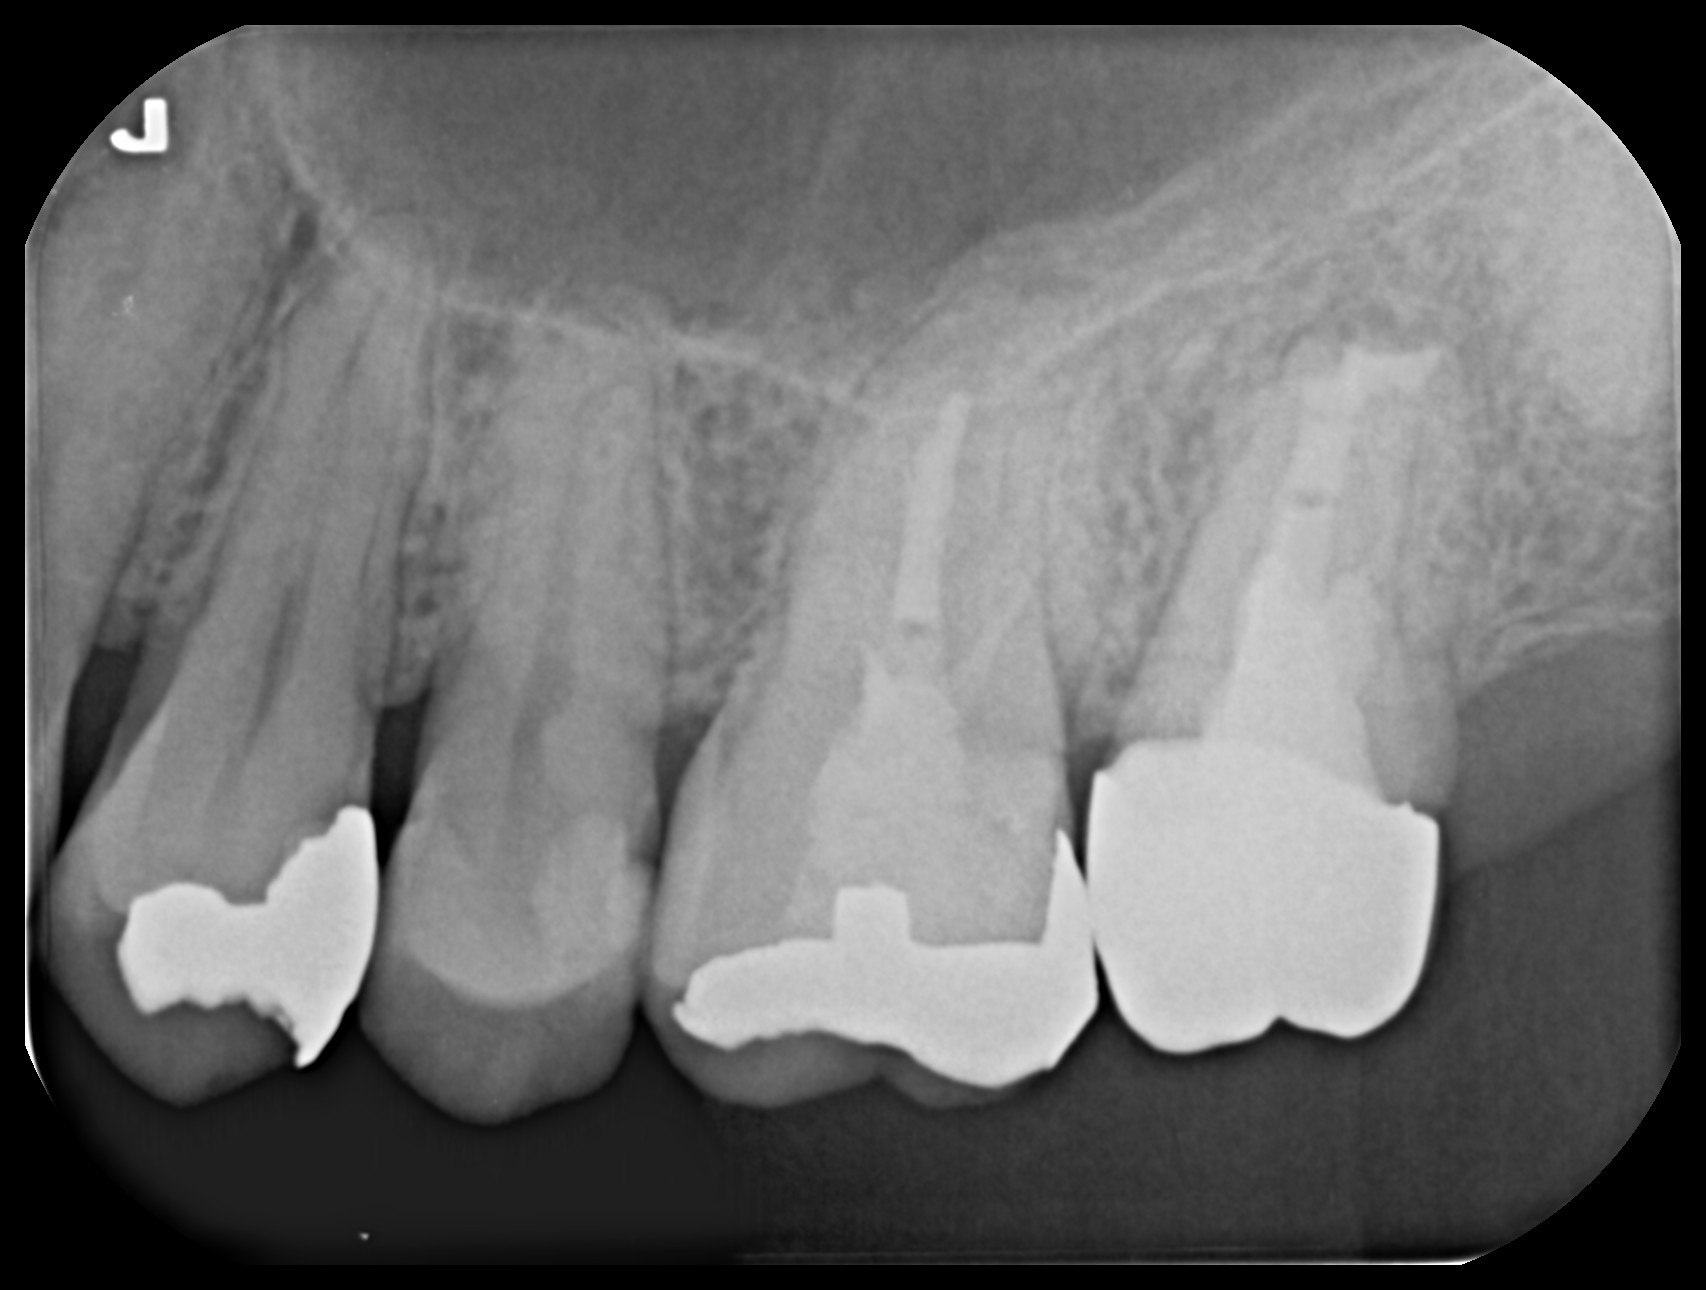

初診時

- 歯の状態:歯質が骨縁上に適切な厚みを持って存在する。根尖の外部吸収様所見

- 隣在歯の状態:失活しているが、病変は認めない。

- 歯根の外部吸収を伴う根尖性歯周炎

- 上顎洞炎を伴う根尖性歯周炎

- 歯根の外側に病原の可能性があり外科的対応を治療計画に組み込む必要がある。

- 根尖部での外部吸収により根尖の拡大を認めるため細菌の押し出しに配慮した手技が求められる。

術直後のレントゲンと処置後の状態

術後のレントゲン